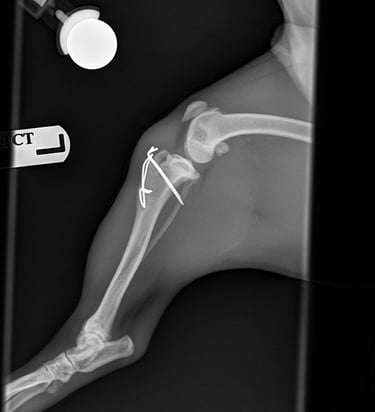

Lateral radiographs revealed a complete avulsion of the left tibial crest (Fig. 1), along with a mild lesion at the distal pole of the patella. For comparison, a lateral view of the right limb is included, demonstrating a normal appearance of the tibial crest growth plate (Fig. 2).

Fig. 1